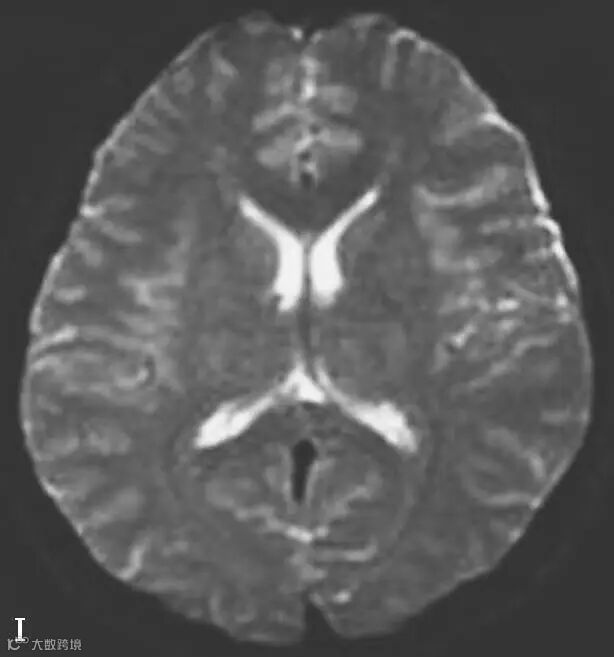

图6-11-1 弥漫性轴索损伤并双侧额部硬膜下积液、双侧顶枕部硬膜下血肿

男,34岁,外伤后7天。A~H(A、B.T2WI,C、D.T1WI,E、F.T2WI-FLAIR,G、H.DWI):左侧岛叶及右侧顶叶白质可见斑片状稍长T1稍长T2信号,边缘不清,FLAIR及DWI呈高信号。双侧额部内板下可见新月形长T1长T2信号,FLAIR及DWI呈低信号。双侧顶枕部内板下可见弧形短T1长T2信号,FLAIR及DWI呈高信号